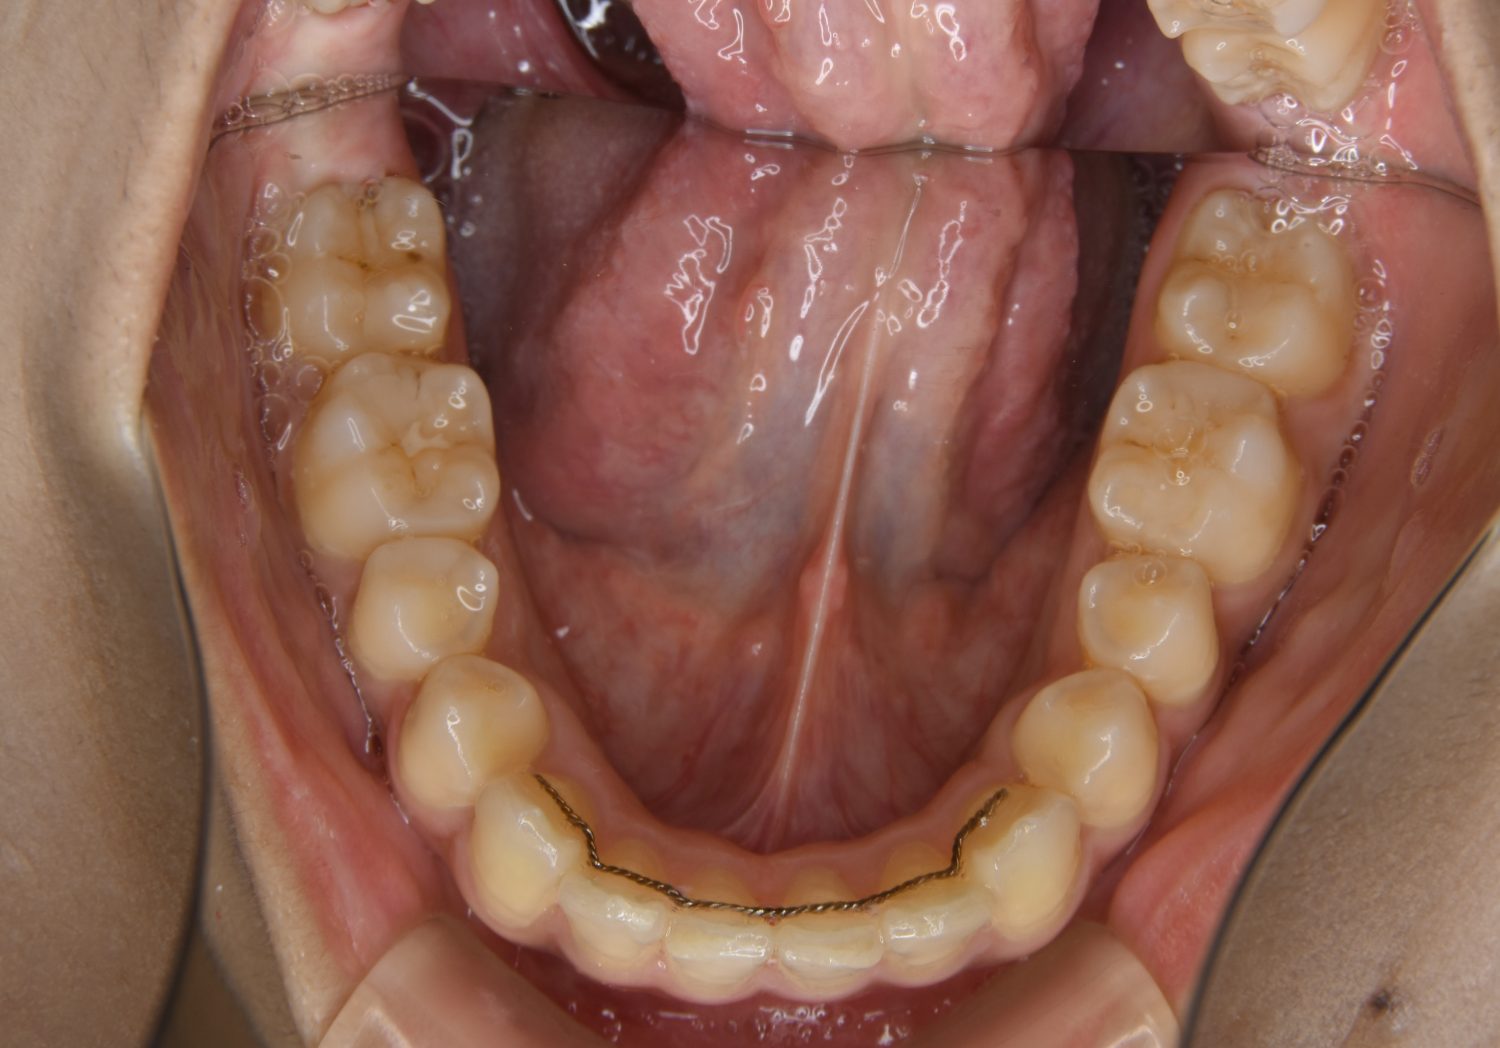

上顎前突の症例紹介①

Before

After

主訴

上の歯が出ている。歯並び全体が気になる。

治療内容

上顎両側第一小臼歯を抜歯し、上下ラビアルブラケット(唇側装置)に矯正用アンカースクリューを併用し治療を行いました。

治療費

1,000,000 円(税込)

治療期間

26ヶ月

通院回数

25回

想定されたリスク

※なし

丸山和宏先生

ピーススマイル矯正歯科

上顎前歯の前突により口元の突出が認められました。上の左右の第一小臼歯を抜歯し上顎前歯を後退させることで口元の突出感は改善し、咬合も良好な状態となりました。